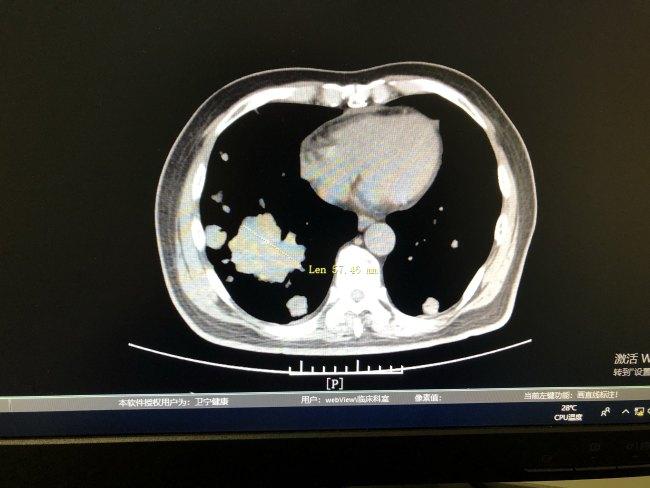

內地一名左腳殘疾的45歲男子(圖),上月底持旅遊簽證入境泰國後,先後到熱門旅遊點芭堤雅所在的春武里府及接壤緬甸的春蓬府行乞,至周一被捕。涉事男子承認行乞,警方在其身上搜出7,895泰銖(約1,964港元),並以「在泰借他人同情心行乞討錢」作出處罰,之後會將其遣返。泰國政府2016年起實施新例打擊行乞集團,警方會逮捕任何國籍行乞者,罰款1萬泰銖(約2,488港元)及監禁1個月。